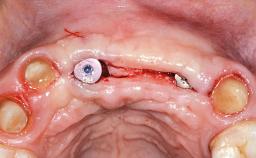

This 20-year-old woman was referred to our department in July 2006. Four months earlier, she had experienced dental trauma to the anterior maxilla when traveling in South America. The emergency treatment included emergency root canal treatment of teeth 12 and 11. Tooth 21 was also subjected to endodontic treatment later. At the initial examination, the patient was not in pain but reported increased mobility of tooth 12. The clinical examination revealed a high smile line, medium thickness of the soft tissue, and rectangular tooth forms. Discoloration of tooth 12 was evident. The periapical radiograph provided by the referring dentist indicated a fracture line at both teeth 12 and 11. A cone-beam computed tomography (CBCT) scan confirmed these fractures. No pathology was found to be associated with tooth 21.